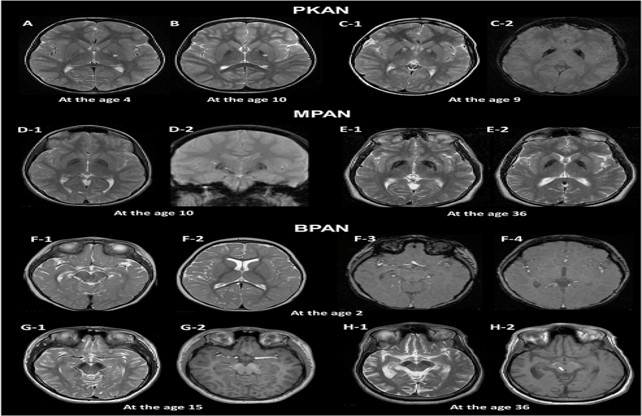

- Brain MRI: This very detailed picture of the brain which helps doctors see if there is a problem with the pituitary gland or the brain that might be causing GH deficiency.